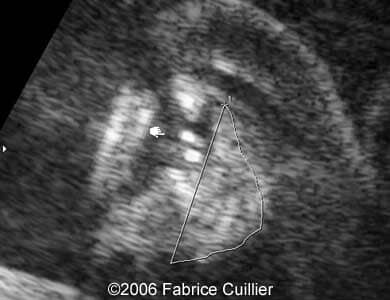

Pictures 1, 2. Coronal planes through lips and nose.

Pictures 3, 4. 2D and 3D pictures showing unilateral cleft lip.